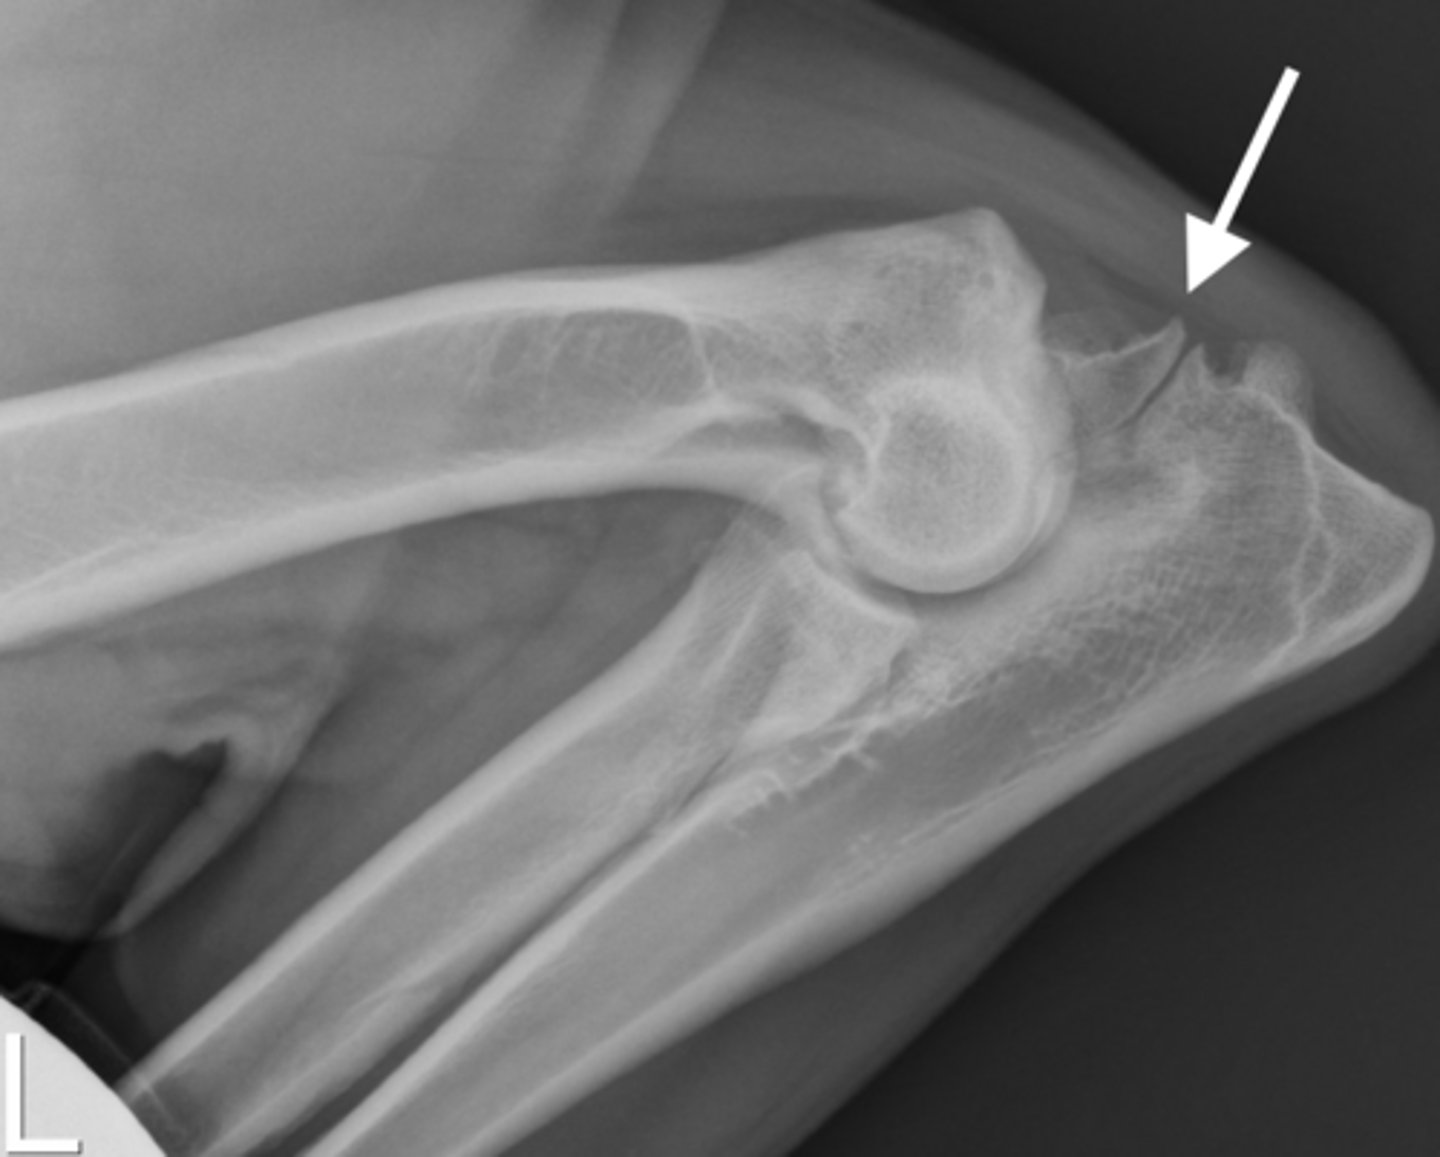

Identify the joint changes?

Monoarthrosis - Osteoarthritis - smooth regular bone less swelling

Erosive

Erosive or non erosive?